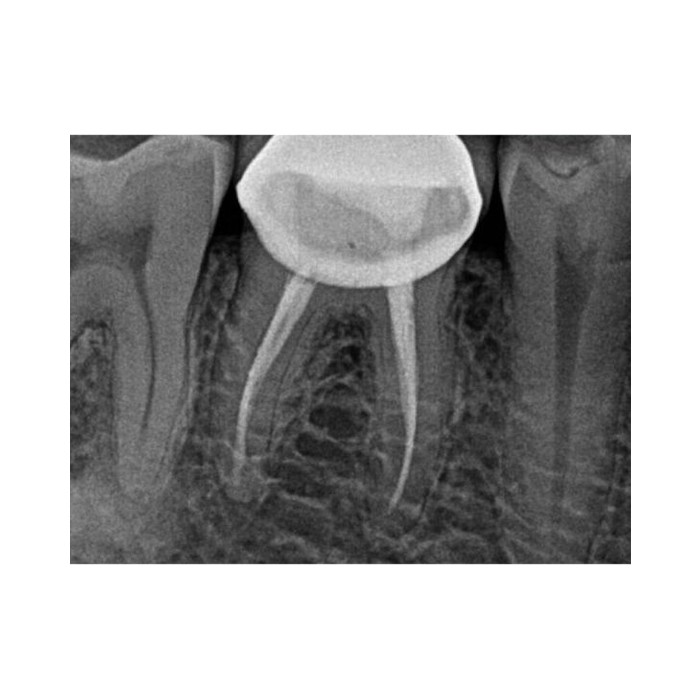

Ключевое преимущество RVG 5200 — высокая разрешающая способность 16 пар линий/мм. Это означает исключительную детализацию снимка, позволяющую четко визуализировать анатомические структуры, тонкие корневые каналы, начальные стадии кариеса и минимальные изменения в периапикальных тканях. Ваша диагностика становится более точной и уверенной.

В чем разница между 16 пар/мм и другими показателями разрешения?

Разрешение в парах линий на миллиметр (пл/мм) — это объективный параметр, характеризующий способность системы различать мелкие детали. Показатель 16 пл/мм является высоким и обеспечивает отличную диагностическую информативность снимков, необходимую для эндодонтии, пародонтологии и выявления скрытого кариеса.